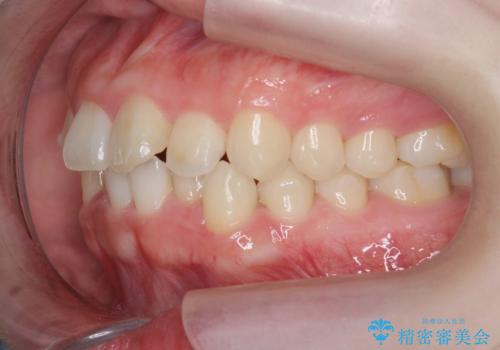

- ねじれの目立つ前歯の見た目を改善したいと矯正治療を希望され来院されました。

がたつきの改善をマウスピース矯正インビザラインで行っていきます。

ガタつきの改善はもちろん、歯列全体のアーチも放物線状にきれいに排列し審美性を向上させることができました。